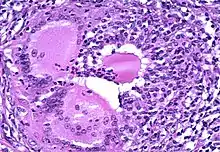

The most common and helpful way to diagnose thyroiditis is first for a physician to palpate the thyroid gland during a physical examination. Laboratory tests allow doctors to evaluate the patient for elevated erythrocyte sedimentation rates, elevated thyroglobulin levels, and depressed radioactive iodine uptake (Mather, 2007). Blood tests also help to determine the kind of thyroiditis and to see how much thyroid stimulating hormone the pituitary gland is producing and what antibodies are present in the body. In some cases, a biopsy may be needed to find out what is attacking the thyroid.